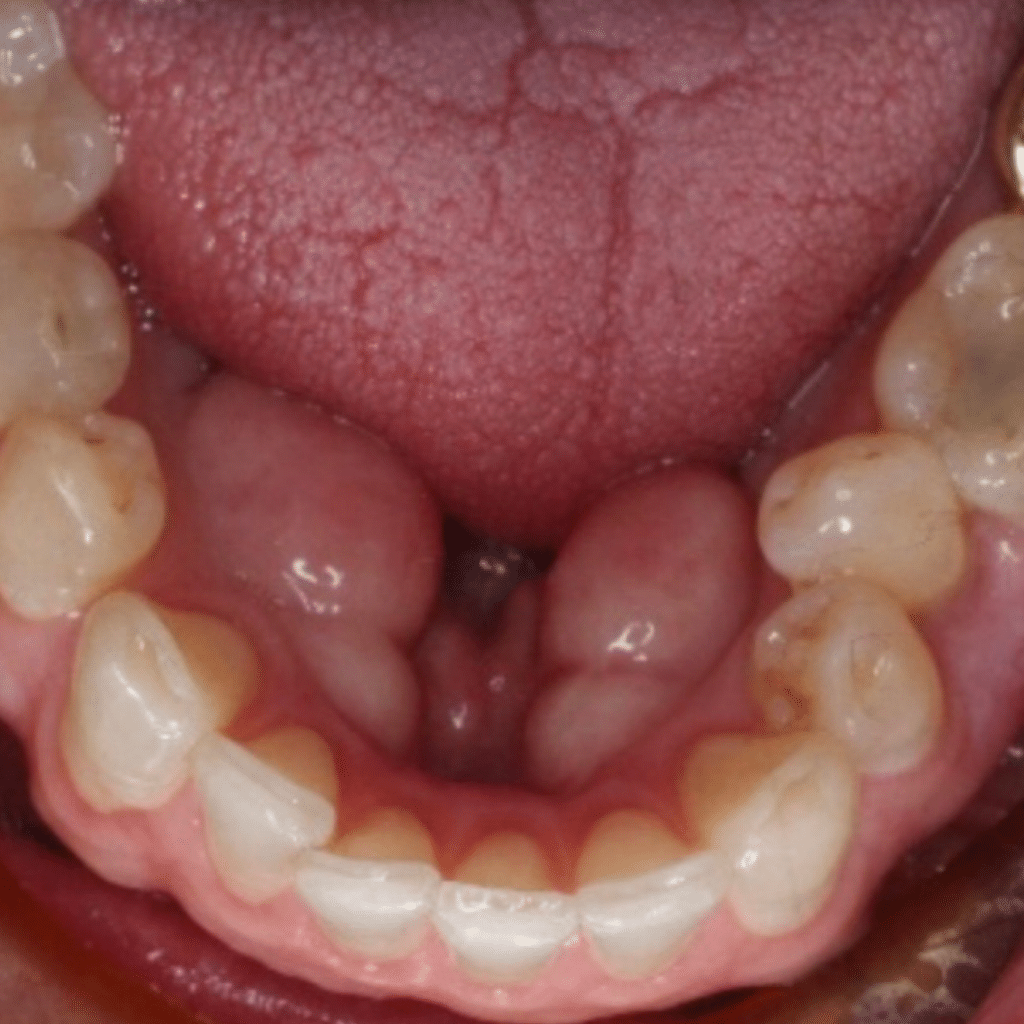

A perfect smile revealinvolving pulpotomies / stainless steel crowns

Before

Look how happy our patient looks after she received the services here at South Airdrie Smiles. We did buildups on her teeth and then recently provided pulpotomies / stainless steel crowns for the two teeth we built up. Her teeth were severely worn down. Now, she can’t seem to get enough of her gorgeous smile!